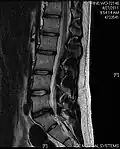

- Magnetic resonance imaging is the gold standard study for confirming a suspected LDH. With a diagnostic accuracy of 97%, it is the most sensitive study to visualize a herniated disc due to its significant ability in soft tissue visualization. MRI also has higher inter-observer reliability than other imaging modalities. It suggests disc herniation when it shows an increased T2-weighted signal at the posterior 10% of the disc. Degenerative disc diseases have shown a correlation with Modic type 1 changes. When evaluating for postoperative lumbar radiculopathies, the recommendation is that the MRI is performed with contrast unless otherwise contraindicated. MRI is more effective than CT in distinguishing inflammatory, malignant, or inflammatory etiologies of LDH. It is indicated relatively early in the course of evaluation (<8 weeks) when the patient presents with relative indications like significant pain, neurological motor deficits, and cauda equina syndrome. Diffusion tensor imaging is a type of MRI sequence used for detecting microstructural changes in the nerve root. It may be beneficial in understanding the changes that occur after herniated lumbar disc compresses a nerve root, and might help in differentiating the patients that need surgical intervention. In patients with a high suspicion of radiculopathy due to lumbar disc herniation, yet the MRI is equivocal or negative, nerve conduction studies are indicated.[44] T2-weighted images allow for clear visualization of protruded disc material in the spinal canal.

MRI scan of large herniation (on the right) of the disc between L4 and L5 vertebrae -

A rather severe herniation of the L4–L5 disc -

Example of a herniated disc at L5–S1 in the lumbar spine